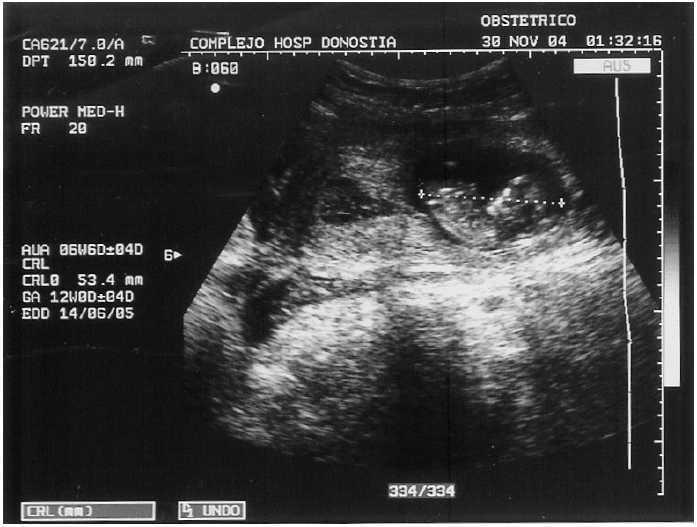

Al ingreso presenta palidez cutánea y de mucosas, mareos y sudación fría. La presión arterial repetida es de 80/50 y 90/60 mmHg, con 96 lat/min. Refiere una amenorrea de 8 + 6 s. El abdomen se encuentra defendido y con signo de Blumberg (+). Al tacto vaginal, el útero se encuentra en anteversión, aumentado respecto a la amenorrea referida; la movilización cervical y la exploración del fondo de saco de Douglas era muy dolorosa. La ecografía vaginal muestra un útero en anteversión, cavidad vacía con reacción decidual. En la zona del cuerno izquierdo, a nivel miometrial, se aprecia un saco gestacional con un embrión en su interior (longitud craneo-caudal [CRL] de 53 mm, que corresponde a 12 semanas de gestación, latido cardíaco positivo y movimientos fetales activos positivos). Los ovarios son normales. Ecográficamente no se visualiza líquido libre (figs. 1 y 2).

Figura 2. Ecografía abdominal: embarazo ectópico cornual. Embrión de 53 mm de longitud craneocaudal, situado excéntricamente en la cavidad uterina. Llama la atención la delgadez del miometrio.